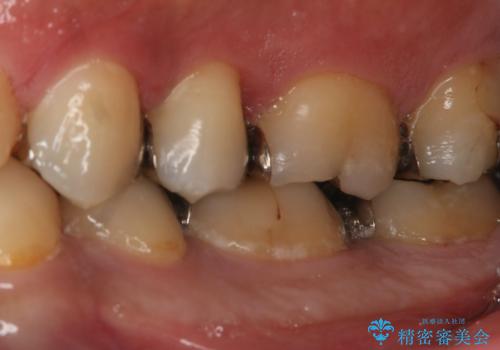

- 左下6番の銀歯が不適であったためやり変えを勧めたところセラミックでの治療を希望された患者様です。

切削量などを考慮し、フルジルコニアクラウンでの治療を選択しました。

う蝕が深く切削量が多くなりましたが痛みなどは起きなかったので、予定通りフルジルコニアクラウンでの治療で進めました。